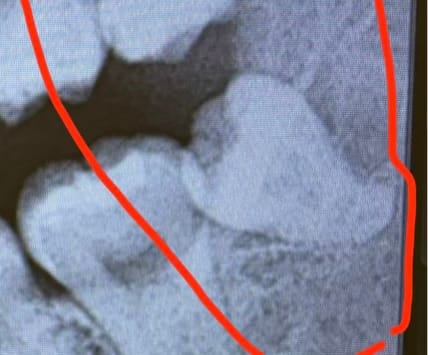

半埋伏とは、歯ぐきに一部埋まっている状態の親知らずです。

私の場合は「斜めに生えている半埋伏」だったため、

特に下の半埋伏の親知らずは、私の場合0.5cm切開してからの、斜めに分割して抜歯しました!